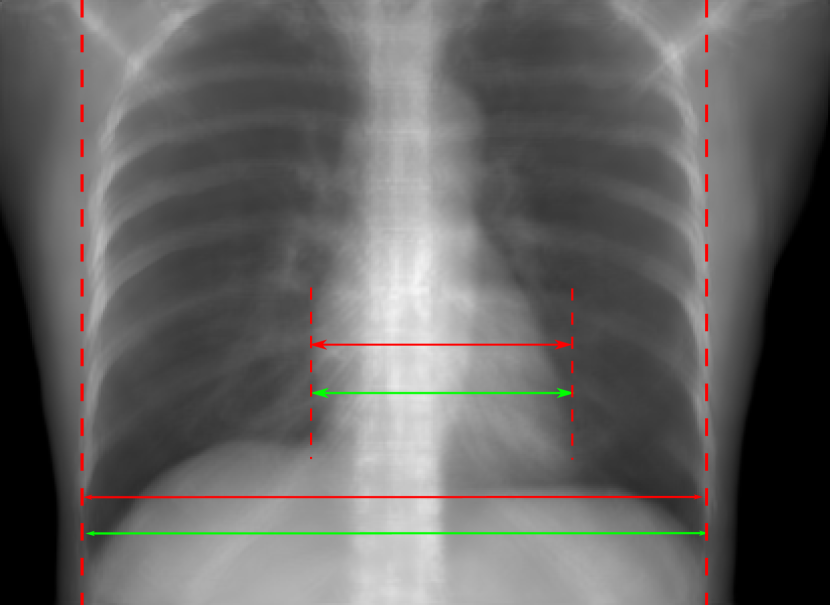

Figure 10: Perspective deformation learning in one exemplary patient case for chest X-ray imaging. The maximal horizontal cardiac diameter and the maximal horizontal thoracic diameter in (b) and (d)-(f) are indicated by the horizontal red lines, while those in the reference image (a) are green lines. The cardiothoracic ratio, RMSE, and SSIM for each image is displayed in its corresponding subcaption.

The results of one patient in chest X-ray imaging are displayed in Fig. 10, where the cardiothoracic ratio is assessed as an exemplary clinical application [32]. In the reference image (Fig. 10(a)), the maximal horizontal cardiac diameter (MHCD) and the maximal horizontal thoracic diameter (MHTD) are indicated by two green horizontal lines. Its cardiothoracic ratio is 0.4237. In the 0superscript00^{\circ} perspective projection image (Fig. 10(b)), all the anatomical structures can be visualized with fine resolution. However, due to perspective deformation, anatomical structures, e.g. the ribs and the spine, are deformed. The deformations are visualized better in the difference image Fig. 10(c). Compared with the ribs and the spine, the heart has less deformation as its location is closer to the isocenter. In Fig. 10(b), the MHCD and the MHTD are indicated by two red horizontal lines, while the green lines are those of the reference image. While the MHCD has changed little from 10.47 cm to 10.16 cm, the MHTD has changed considerably from 24.71 cm to 25.40 cm. As a consequence, the cardiothoracic ratio becomes 0.4002, which is below the normal range of 0.42 - 0.50 [32]. The result of learning perspective deformation from 0superscript00^{\circ} single view is displayed in Fig. 10(d), where the MHCD and the MHTD are 10.63 cm and 24.71 cm, respectively. The MHTD of Fig. 10(d) is the same as that of the reference image. This is also reflected by the difference image Fig. 10(g), where the lower ribs have small errors. However, the upper ribs as well as the spine still have considerable errors. The results of perspective deformation learning from 0&180superscript0superscript1800^{\circ}\&180^{\circ} views in Cartesian and polar coordinates are displayed in Fig. 10(e) and Fig. 10(f), respectively. The measured MHCDs and MHTDs in these two images are very close to the reference ones. Hence, their cardiothoracic ratios, 0.4214 and 0.4240 respectively, are close to the reference ratio as well. In the difference images (Fig. 10(h) and Fig. 10(i)), the errors of ribs and spine decrease as their boundaries are no longer apparently visible. Nevertheless, Fig. 10(i) has less error than Fig. 10(h), achieving the smallest RMSE value of 3.83. The quantitative evaluation of all the 162 testing datasets is displayed in Tab. II, where learning perspective deformation from two complementary views in polar coordinates achieves the least RMSE 4.98 and highest SSIM 0.9517, demonstrating the superiority of learning perspective deformation from two complementary views in polar coordinates.

The TransU-Net results are displayed in Figs. 10(j)-(l). Compared with their corresponding Pix2pixGAN results, the TransU-Net prediction images are more blurry, although the same perceptual loss is used. The error images in Figs. 10(m)-(o) indicate that TransU-Net reduces perspective deformation better with complementary views than a single view. The quantitative evaluation in Tab. II shows that TransU-Net cannot effectively reduce perspective deformation with a single view. With complementary views in both Cartesian and polar coordinate systems, TransU-Net achieves comparable performance, which is still considerably worse than that of Pix2pixGAN. The inferior performance of TransU-Net to Pix2pixGAN on the chest data is potentially caused by the repetitive nature of the segmental rib anatomy, which leads TransU-Net to be ineffective in extracting position-dependent features.